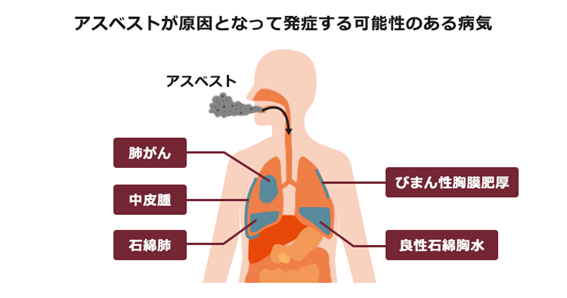

胸膜肥厚の最も重要な原因の一つに、アスベスト(石綿)へのばく露があります。アスベストは、かつて建材や摩擦材などに広く使用されていた天然の鉱物繊維ですが、その微細な繊維を吸い込むことで、肺や胸膜に様々な健康被害を引き起こすことが知られています。アスベスト繊維が胸膜に到達すると、炎症反応を引き起こし、長期間にわたる刺激によって胸膜の線維化が進行し、胸膜肥厚が生じます。

特に、アスベストばく露によって生じる胸膜肥厚は「胸膜プラーク(胸膜肥厚斑)」と呼ばれる特徴的な病変として現れることがあります。胸膜プラークは、アスベストばく露から数十年という長い潜伏期間を経て発症することが多く、アスベスト関連疾患の診断において重要な所見となります。胸膜プラーク自体は良性疾患であり、通常は症状を伴いませんが、アスベストばく露の明確な証拠となるため、その後の肺がんや悪性胸膜中皮腫などの重篤な疾患の発症リスクを評価する上で極めて重要です。

アスベストばく露による胸膜肥厚は、胸膜プラークの他にも、びまん性胸膜肥厚や良性石綿胸水(胸膜炎)として現れることがあります。これらの病変は、アスベスト繊維が胸膜に沈着し、慢性的な炎症を引き起こすことで発生します。特にびまん性胸膜肥厚は、広範囲にわたる胸膜の肥厚により、肺の拡張が制限され、呼吸機能の低下を招くことがあります。

過去にアスベスト業務に従事していた方が、アスベスト関連疾患(肺がん、中皮腫、石綿肺、びまん性胸膜肥厚など)を発症した場合に適用される制度です。胸膜プラークがある場合、アスベストばく露の重要な所見として、肺がんなどの労災認定の判断材料となることがあります。労災認定されると、療養補償給付、休業補償給付、障害補償給付、遺族補償給付などが支給されます。

労災保険の対象とならない方(自営業者や一般住民など)がアスベスト関連疾患を発症した場合に適用される制度です。この制度では、医療費、療養手当、葬祭料、遺族弔慰金などが支給されます。びまん性胸膜肥厚も救済の対象となる疾病の一つです。